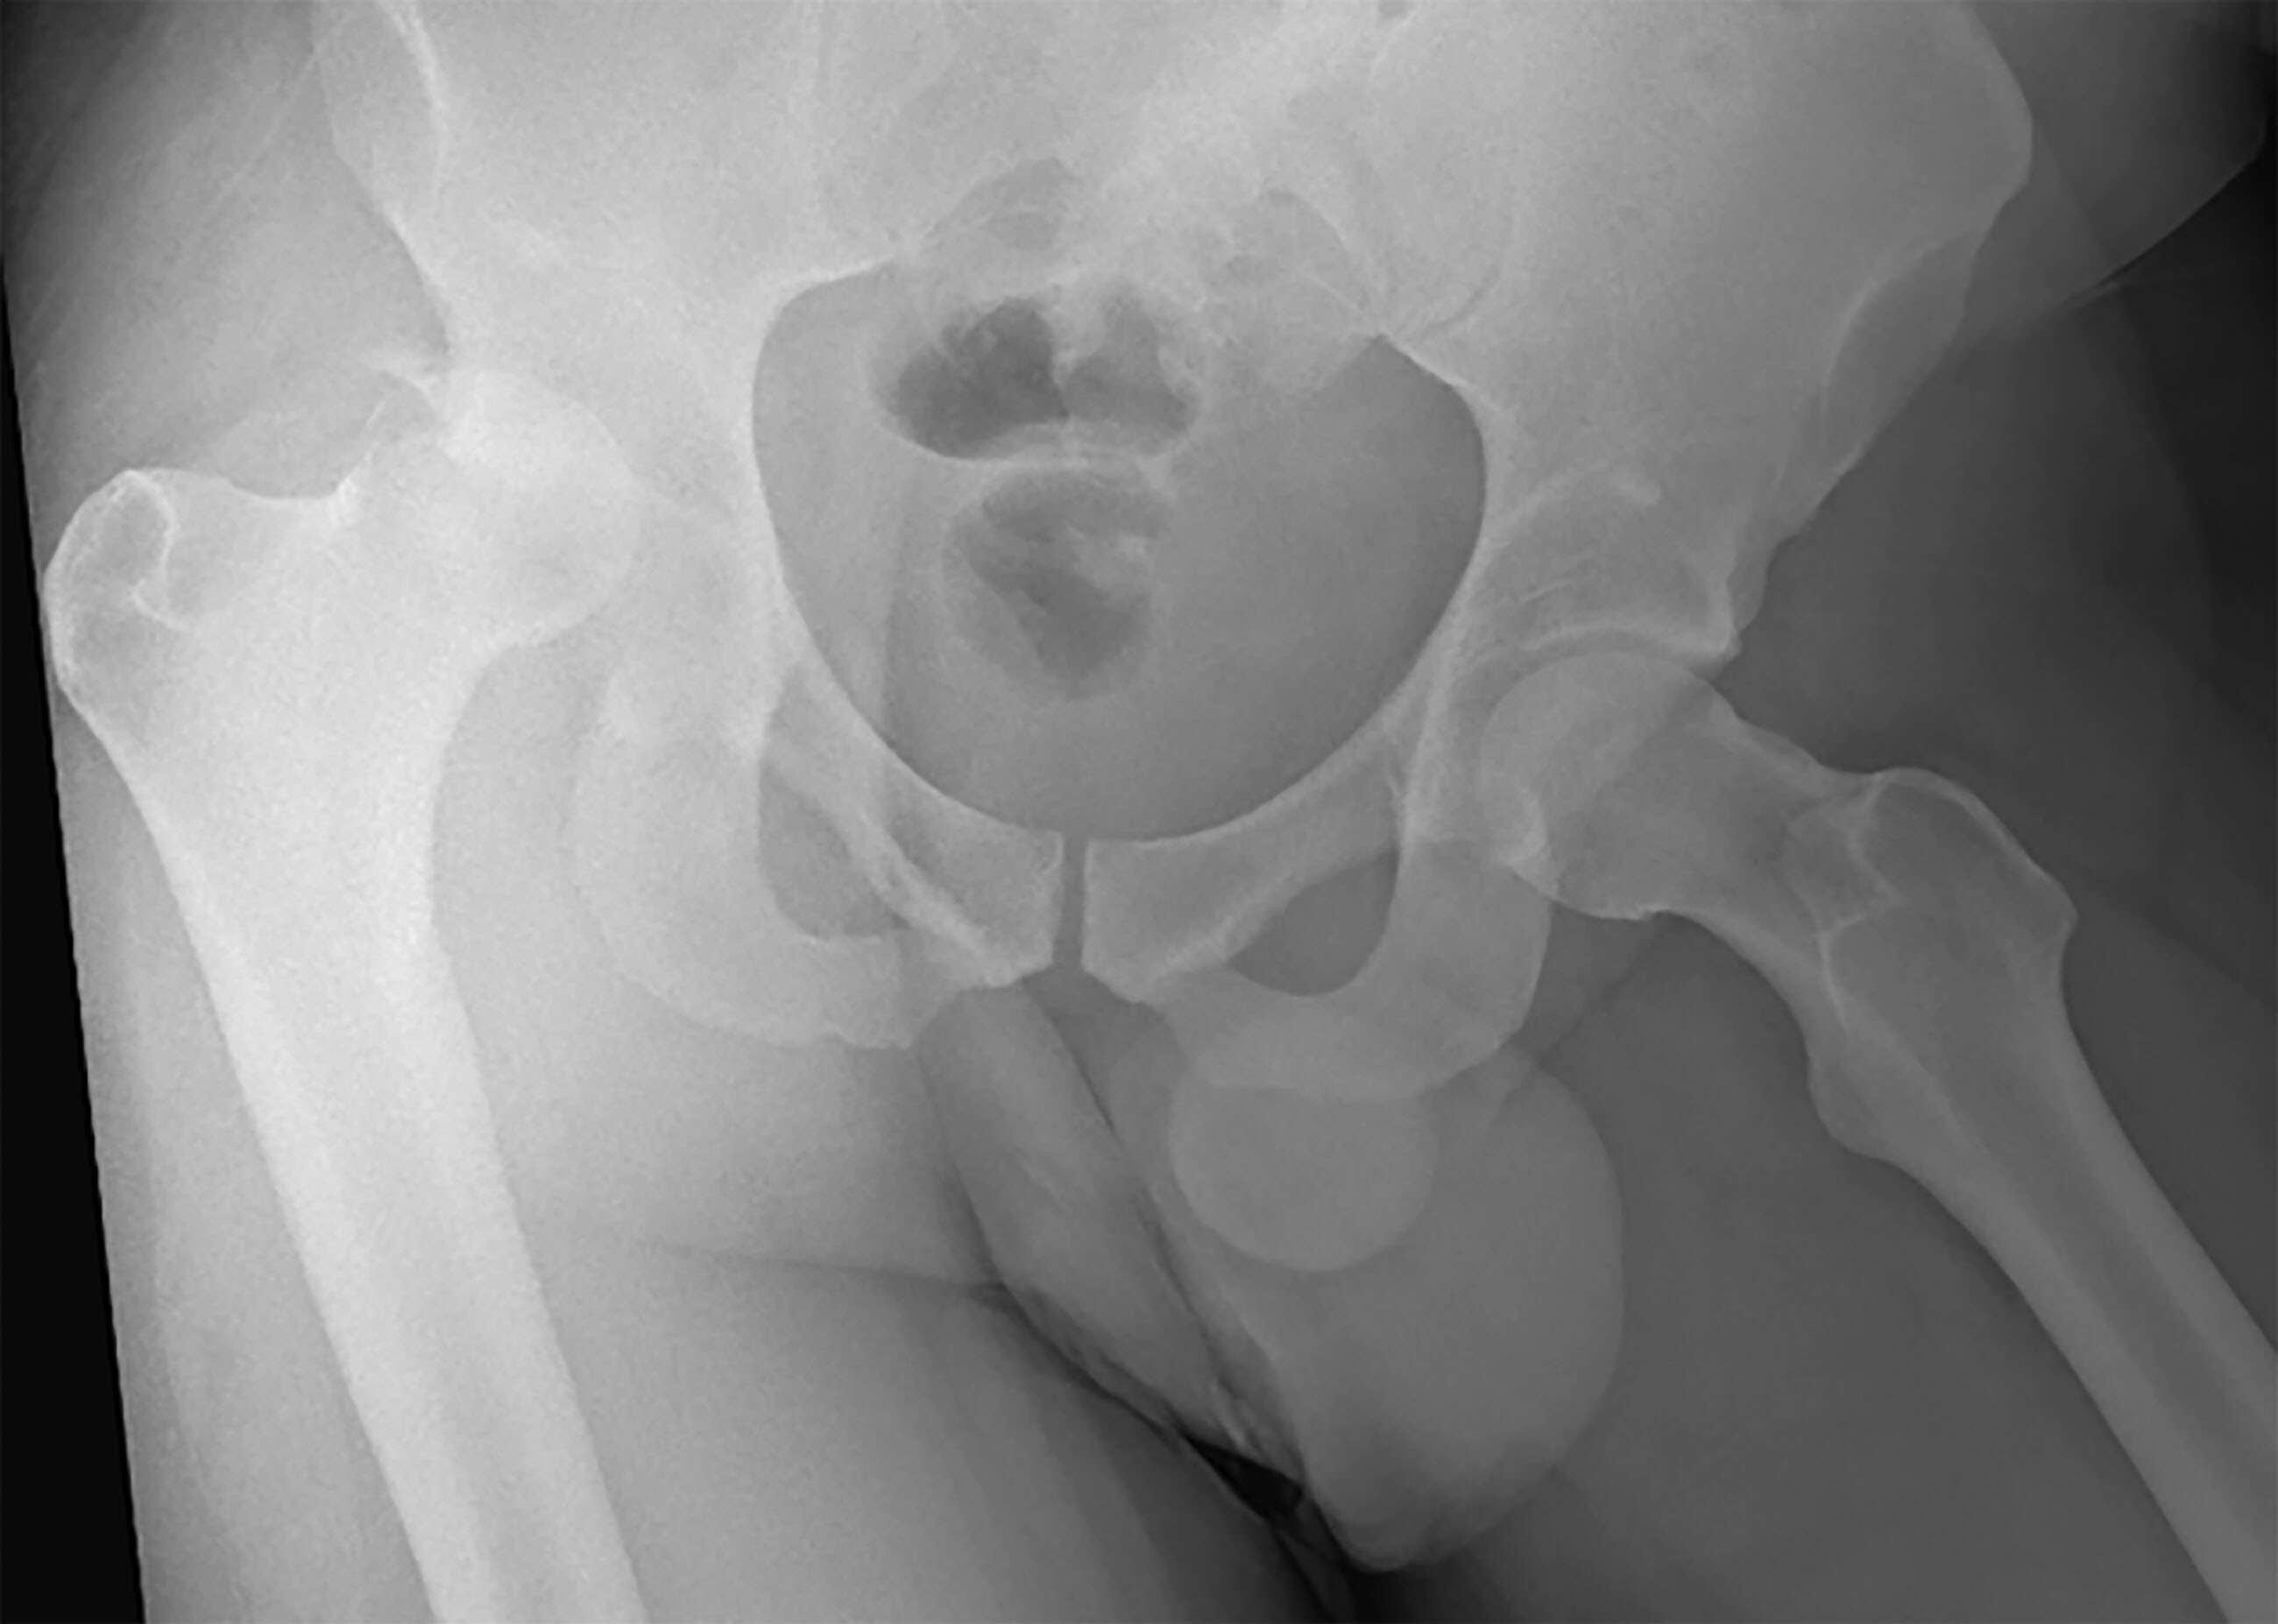

HD should be suspected in the patient presenting with the hip in flexion, internal rotation, and adduction (posterior HD) or the patient with the hip in external rotation with a small amount of flexion and abduction (anterior HD).27 AP plain and lateral films should be obtained to diagnose HD and rule out fracture. (See Figure 3.) If there is a high degree of suspicion of HD, specifically an anterior dislocation, CT should be performed since AP radiographs are unable to diagnose most anterior HDs.28

Figure 3. Posterosuperior Right Femoral Head Dislocation with Acetabular Fracture |

![]() |

Image used with permission from Dr. Dennis Hanlon. |

Femoral neck or acetabular fractures combined with HDs are extremely rare, occurring mainly in young adults from high-speed motor vehicle collisions.29 Do not attempt reduction in the ED since they require reduction and fixation in the operating room. Those with acetabular fractures and dislocation have a higher rate of requiring total hip arthroplasty in the future at 26%, and a higher incidence of developing avascular necrosis (AVN) around 9.2% when compared to those with only acetabular fracture.30